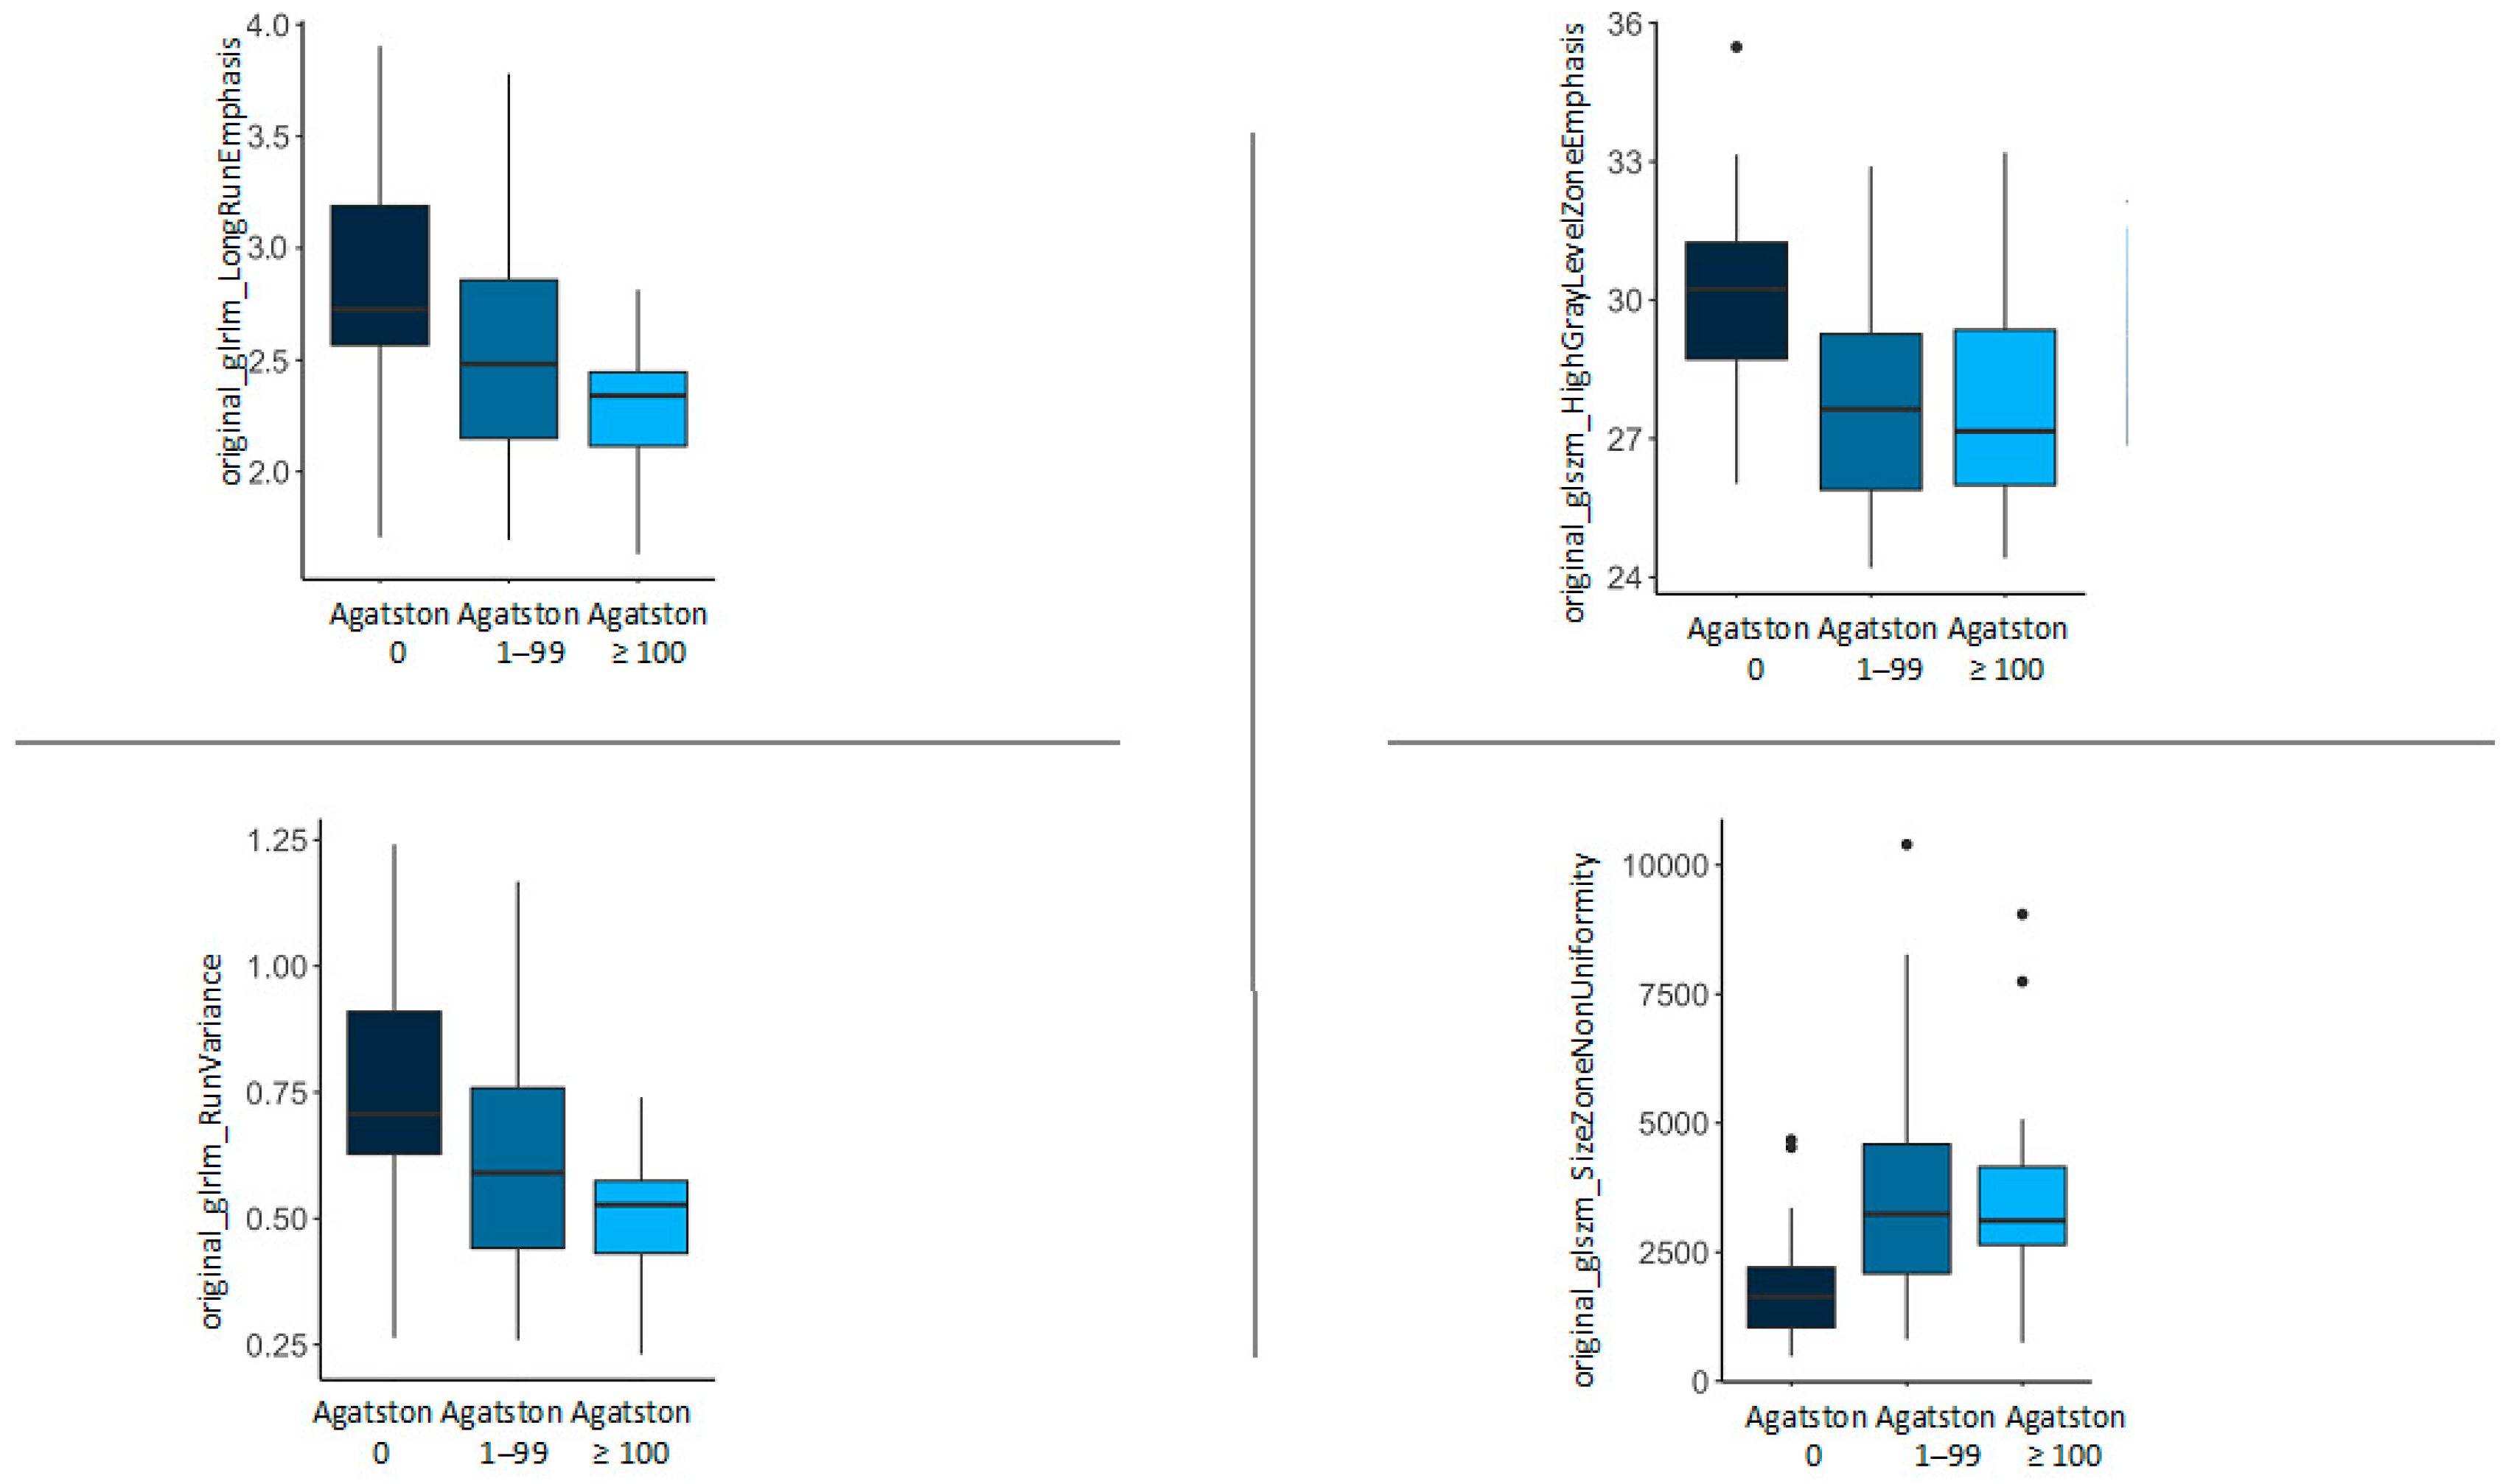

| Feature | Agatston 0 | Agatston 1–99 | Agatston ≥ 100 | p-Value |

|---|---|---|---|---|

| original_glrlm_LongRunEmphasis | 2.82 (0.51) | 2.55 (0.56) | 2.27 (0.34) | 0.013 |

| original_glrlm_RunVariance | 0.74 (0.23) | 0.62 (0.25) | 0.50 (0.15) | 0.013 |

| original_glszm_HighGrayLevelZoneEmphasis | 30.16 (2.32) | 27.68 (2.42) | 27.83 (2.43) | 0.003 |

| original_glszm_SizeZoneNonUniformity | 1893.05 (1156.82) | 3815.24 (2487.78) | 3817.49 (2390.38) | 0.005 |